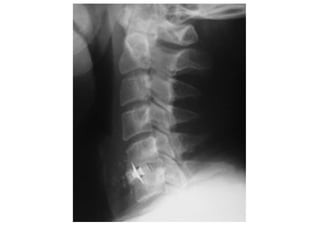

INCIDÊNCIA COLUNA

INCIDÊNCIA COLUNA CERVICAL

PERFIL

ESTRUTURAS MAIS DEMONSTRADAS: Estudo funcional para demonstrar os

movimentos das vértebras cervicais.

extensão flexão